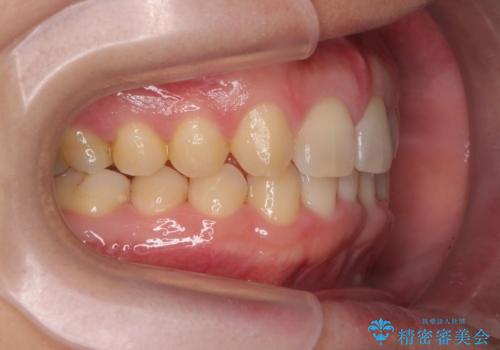

前歯のすき間 歯のがたつき

- 前歯のすき間とがたつきを主訴に来院。

右上の前歯は過去にがたつきがあったとのことで抜いてしまっていました。

歯の数を合わせるために、下の歯を1本抜いて矯正しています。

下の前歯を抜歯したことでブラックトライアングルができましたが、仕上げにIPRを加えることで目立たなくすることができました。